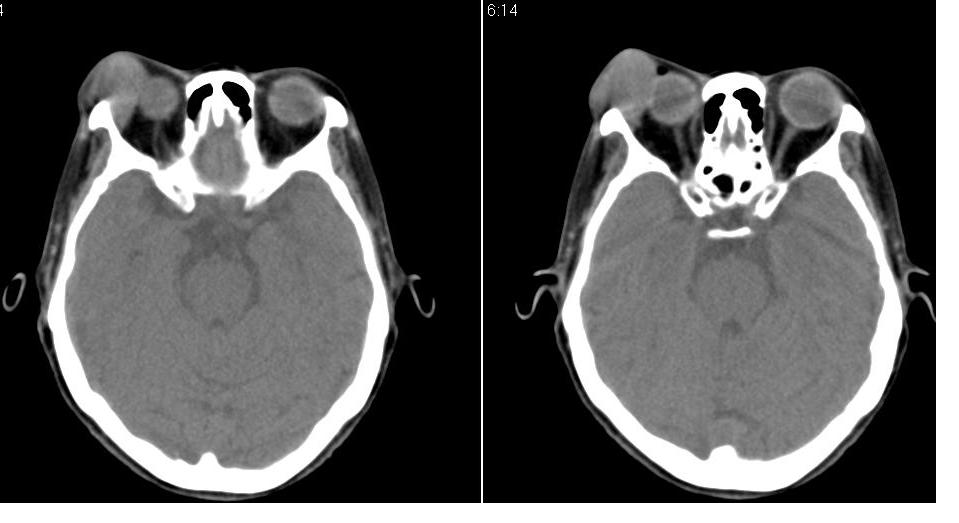

以下是引用zhw974247在2007-5-14 19:34:00的发言:[br]泪腺肿瘤在眶原发性肿瘤中发病率最高,而泪腺混合瘤又是其中最常见者,有良性及恶性二种。良性泪腺混合瘤多见于中年人,病程长,来源于泪腺管或腺泡,也可以起源于副泪腺及先天性胚胎组织残留(泪腺原基)。恶性泪腺混合瘤缺少或无完整的包膜,肿块与眶缘发生粘连,粘连部眶缘有压痛。瘤组织除有良性泪腺混合瘤的结构外,还有癌变的组织构成。瘤组织向眶内浸润,破坏骨质,可发生全身转移,严重者向颅内转移,危及生命。[br]